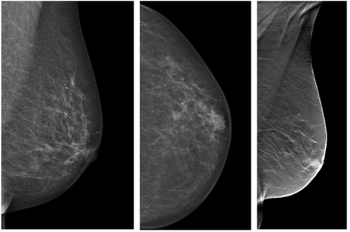

Findings support argument for replacing digital mammography with digital breast tomosynthesis for breast cancer screening.

Both pre- and post-menopausal women who undergo annual screening mammography have fewer late-stage breast cancer diagnoses, fewer interval cancers, and smaller average tumor size.